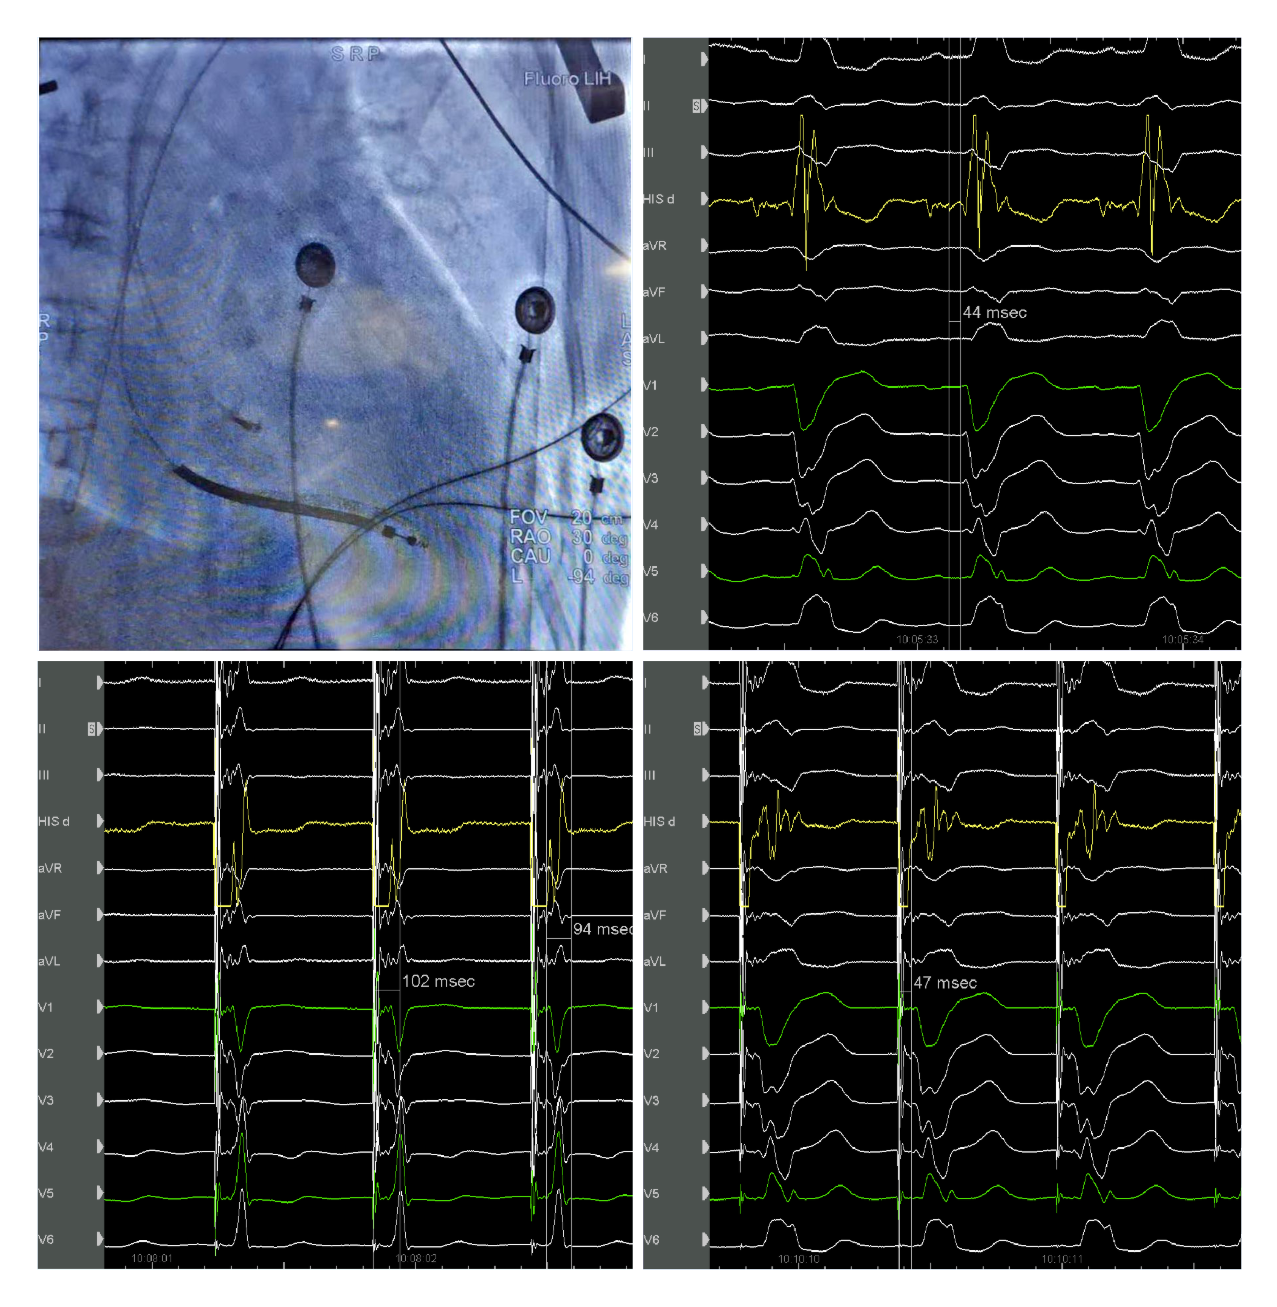

主播福利 起搏团队演示了一例左束支起搏纠正完全性左束支阻滞用于治疗经典CRT适应症的病例。该患者为女性, 69岁,诊断:扩张型心肌病,完全性左束支传导阻滞,心功能III级,心电图显示经典完全性左束支阻滞图形,QRS193ms,心超LVD 73mm,EF 30%,符合CRTD适应症。术中顺利穿刺左侧腋静脉,在C315鞘管导引下3830电极标记到HIS电位,高电压起搏可纠正左束支阻滞,但纠正阈值较高8V/1.5ms。

(上图左上为希氏束的影像位置;右上为希氏束电位图;右下为低电压选择性希氏束起搏波型与自身一致;左下为高电压8V/1.5ms希氏束起搏纠正完左)

随后3830导线往心尖方向前移1cm拧入,同时监测起搏图形及单极阻抗,到位后起搏心电图显示不完全性右束支阻滞图形,左束支阻滞消失,测量V5导联左室达峰时间84ms,单双极高低电压起搏一致,提示夺获了左束支,夺获阈值0.7V/0.5ms。

(上图中左上为单极高电压起搏,右上为单极低电压起搏,左下为双极高电压起搏,右下为双极低电压起搏)